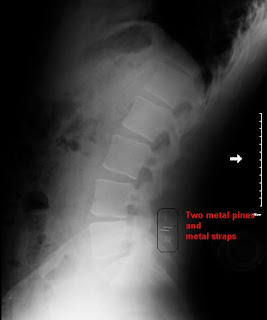

I've included the various X-rays that were taken of my spine last week, as well a composite image of post and 6 week hyper extension positions.

(Hyper extension - X-Ray courtesy of BCH)